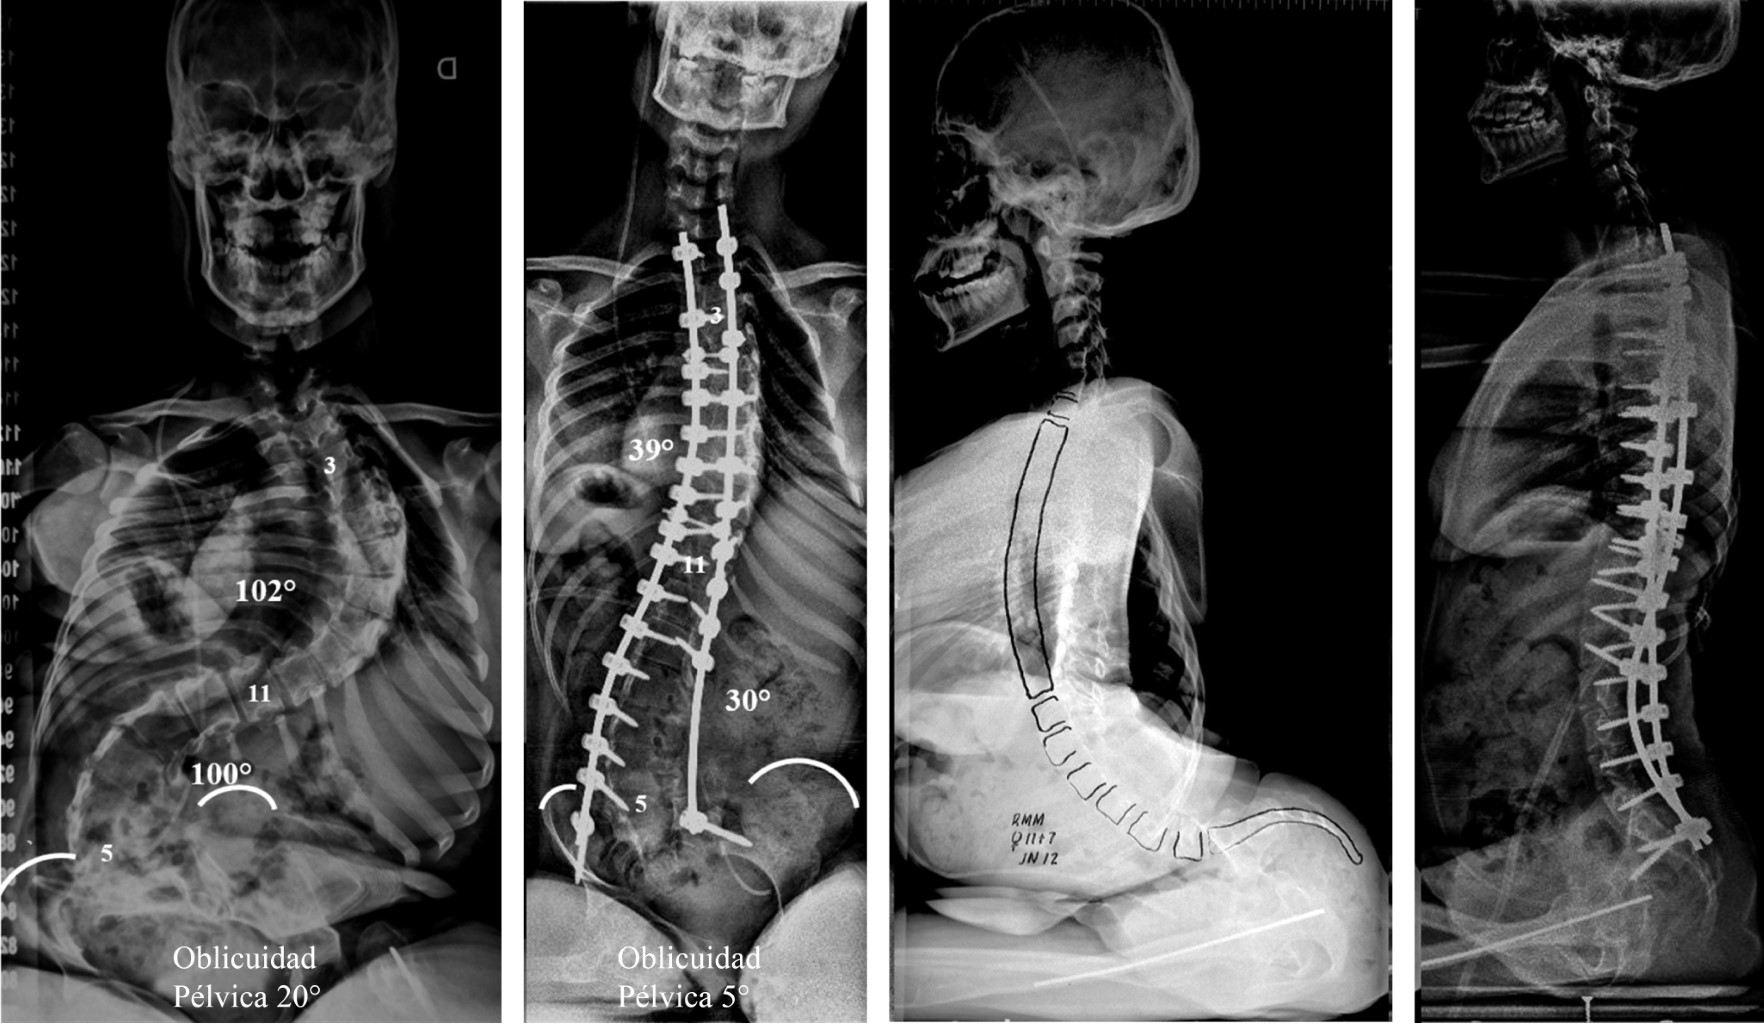

Objective: The aim of the study was to evaluate the outcomes and complications in patients with myelomeningocele who have undergone spinal fusion for neuromuscular scoliosis. Material and methods: Retrospective study of 40 consecutive patients with myelomeningocele with neuromuscular scoliosis who underwent spinal arthrodesis, treated at our center between July 1991 and July 2028. Results: Mean follow up was 10 years. There were 19 male and 21 females. The average age at operation was 13 years. The mean preoperative scoliosis curve was 90o. At last follow up, the mean scoliosis curve was 43o. Mean correction of 52%. The average of pelvic obliquity was 19o. At last follow up de obliquity was 9o. Mean correction of 53%. The mean preoperative coronal balance was 28.4 mm. At the last follow up it was 17 mm. Mean correction of 40%. The mean preoperative kyphosis was 50o. At the last follow up it was 41o. Mean correction of 18%. The mean preoperative sagittal balance was 63.3 mm. At the last follow up it was 38.3 mm. Mean correction of 40%. There were 13 complications (32.5%), with infection being the most frequently observed complication. Conclusions: The goals of the spinal surgery in patients with MMC are to obtain a stable, balanced and painless spinal fusion. Although the surgical treatment of these patients remains difficult, it is associated with high complication rate.

Figure 1